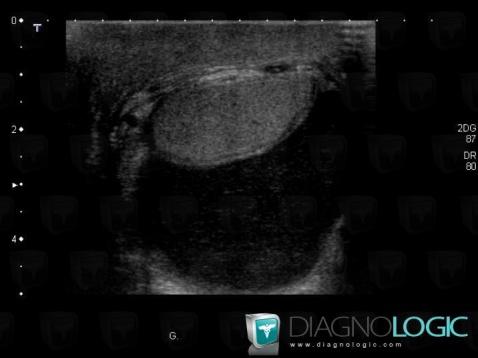

The images below illustrate this case for diagnoses Hydrocele, for the modalities (US)

- Diagnosis Hydrocele, Location(s) Scrotum, with gamuts Cystic extratesticular mass